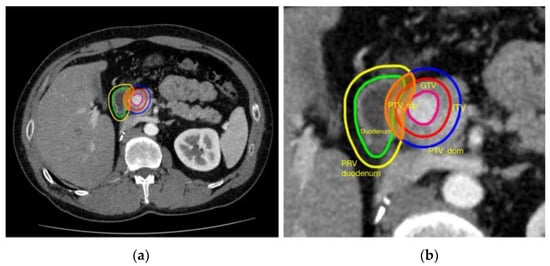

- Brunner, T.B.; Nestle, U.; Adebahr, S.; Gkika, E.; Wiehle, R.; Baltas, D.; Grosu, A.L. Simultaneous integrated protection: A new concept for high-precision radiation therapy. Strahlenther. Onkol. 2016, 192, 886–894. [Google Scholar] [CrossRef]

- Simoni, N.; Micera, R.; Paiella, S.; Guariglia, S.; Zivelonghi, E.; Malleo, G.; Rossi, G.; Addari, L.; Giuliani, T.; Pollini, T.; et al. Hypofractionated stereotactic body radiation therapy with simultaneous integrated boost and simultaneous integrated protection in pancreatic ductal adenocarcinoma. Clin. Oncol. 2021, 33, e31–e38. [Google Scholar] [CrossRef]